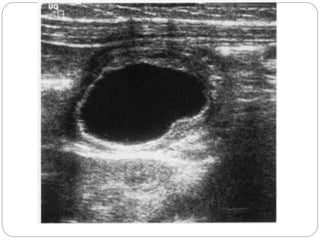

A simple ovariancyst on the right side of the uterus